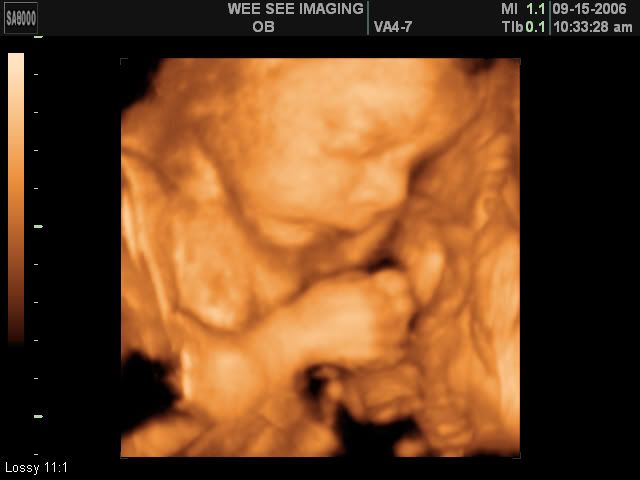

Victoria Rose Kelly

Date Due: December 15, 2006